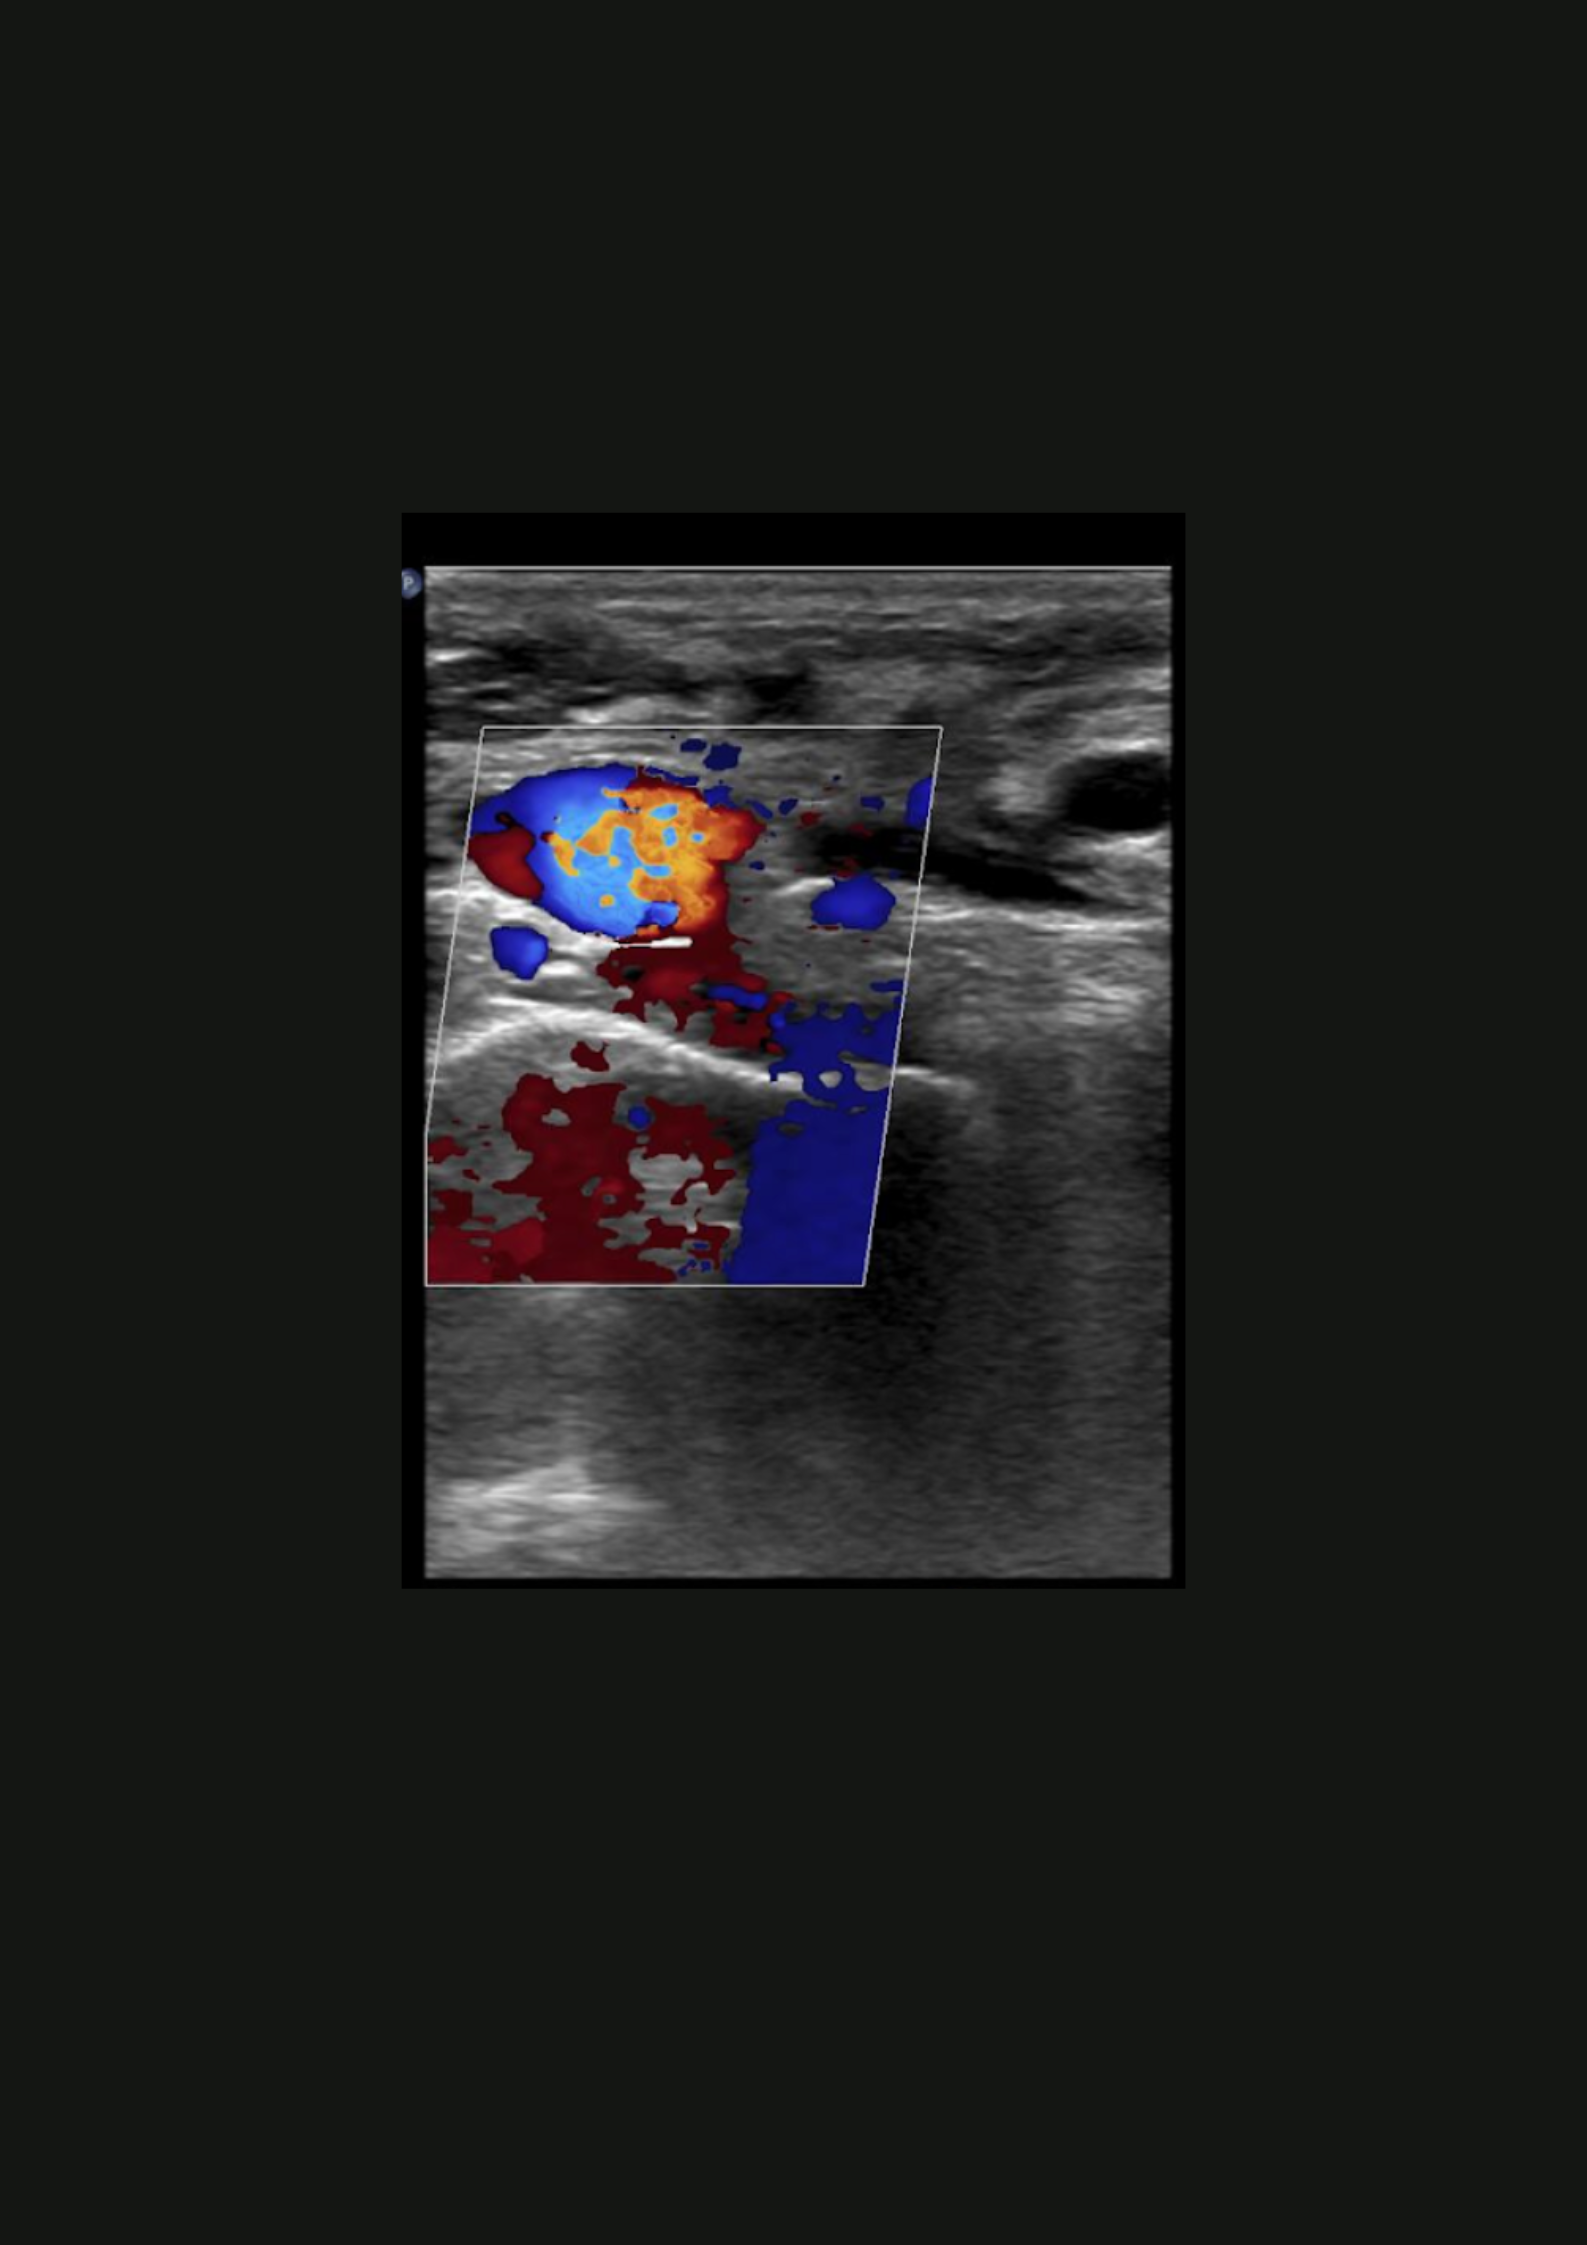

Hallazgos ecográficos

En la ecografía no apreciamos alteraciones musculares pero observamos dificultad para la compresión de la vena subclavia derecha en extensión.

Trombosis venosa profunda de sublcaiva, innominada, cefálica y yugular derecha.

Se remite a Urgencias del hospital de referencia con hallazgos de coagulación: INR 1.05, fibrinógeno 464, Dímero D 1222; y una ecografía de partes blandas que muestra una trombosis venosa de la vena subclavia derecha y vena innominada, con ligera extensión a la vena yugular derecha y cefálica derecha. Posteriormente, se inicia heparina subcutánea y se realiza fibrinolisis con perfusión de urokinasa. En el estudio de coagulación posterior se determinó una hiperhomocisteinemia y probable síndrome antifosfolípido (Paget-Schroetter).